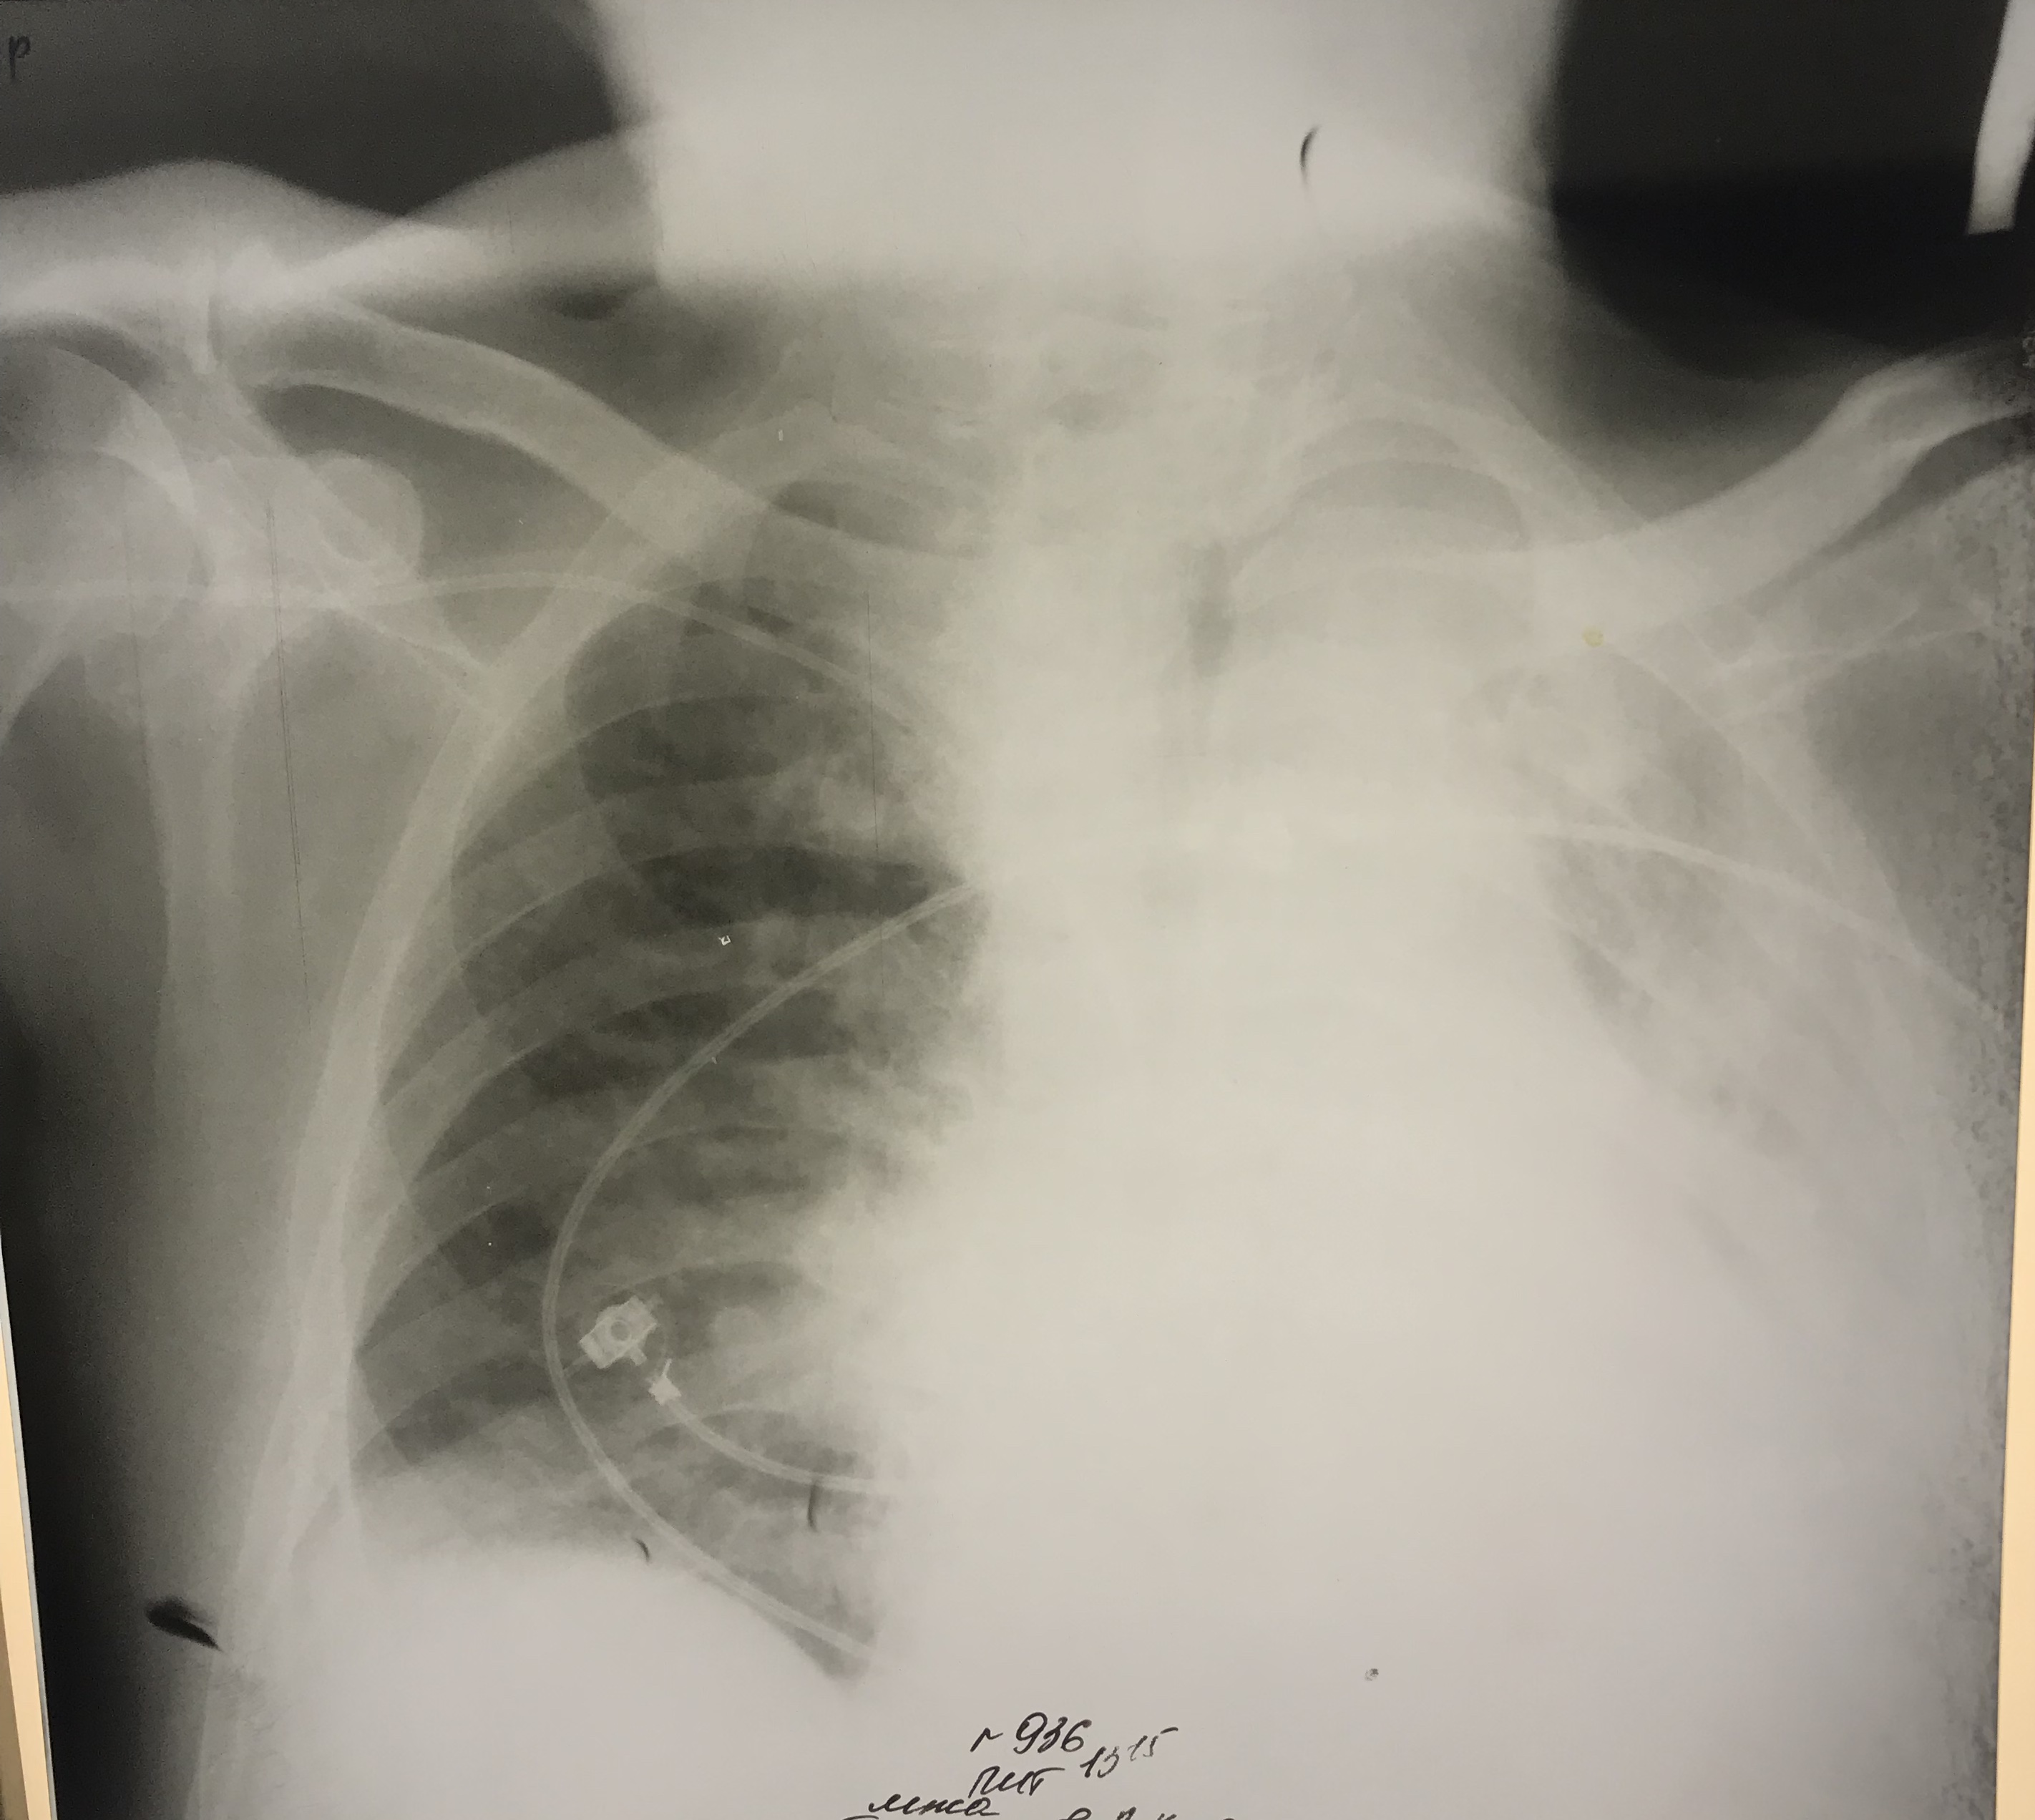

Ателектаз у больного с инсультом

Обсуждалось здесь https://vk.com/club84409679?w=wall-84409679_9427%2Fall